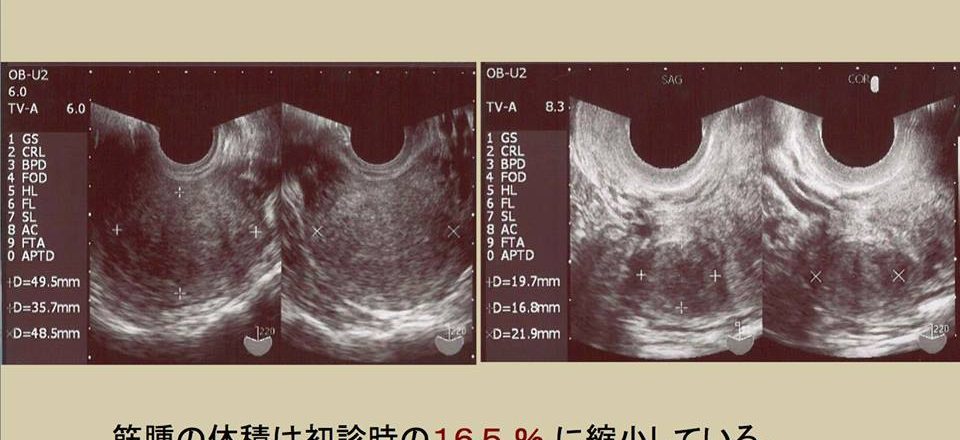

子宮筋腫は生理痛、貧血、そして不妊の大きな原因となります。